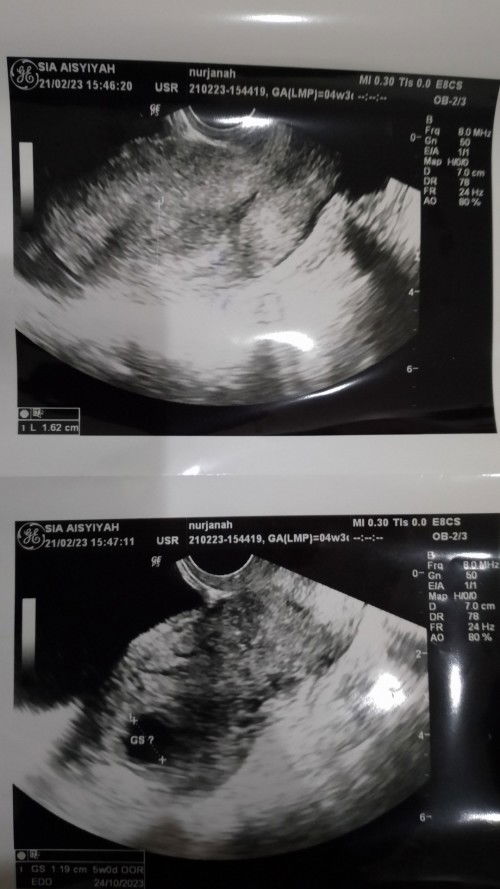

Hpht 21 Januari, tadi pagi sempat tespek dan hasilnya positif. Sore tadi periksa ke dokter mau memastikan apakah iya hamil. Langsung di Usg Transvaginal sama dokternya, ternyata belum terlihat apa2 di rahim. malah ada bulatan kecil di luar rahim. jadi ngeblank, apa iya cuma karena hormon atau kami yang terlalu cepat periksanya ? #seriusnanya #ingintahu #pleasehelp #firstbaby #firstmom ?